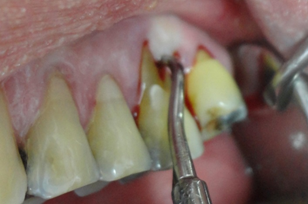

Esta paciente veio ao consultório com a indicação de uma raspagem nesta região. Pois segundo seu Dentista, sua gengiva esta inflamada. Um exame radiográfico foi realizado, mostrando uma grande perda de osso, os dentes apresentavam uma grande mobilidade, com um prognóstico muito sóbrio. O caso da paciente, foi minuciosamente discutida com a paciente, mostrado que os dentes da bateria inferior anterior estavam perdidos, não haveria meios mais, de serem recuperados. Foi um choque no início para a paciente, contudo após um exame geral em sua boca, mostrando as profundas bolsas intraósseas, com inflamações generalizadas, e o risco que ela corria, não somente pela perda dos dentes, mas comprometimentos gerais incluindo problemas sérios cardíacos, ela se conscientizou da necessidade urgente de tratamento.

No início da profilaxia pré-cirúrgica, com as pontas de ultrassom, podemos demonstrar a paciente a necessidade do procedimento indicado. Os dentes praticamente seriam removidos apenas com uma profilaxia rigorosa. Em certos casos, e dependendo dos pacientes, é importante mostrar as alterações patológicas, assim como documentar os procedimentos, que forem realizados. Os dentes foram extraídos, pois, estavam condenados. Apaciente não usava, pois estavam moles e doíam.